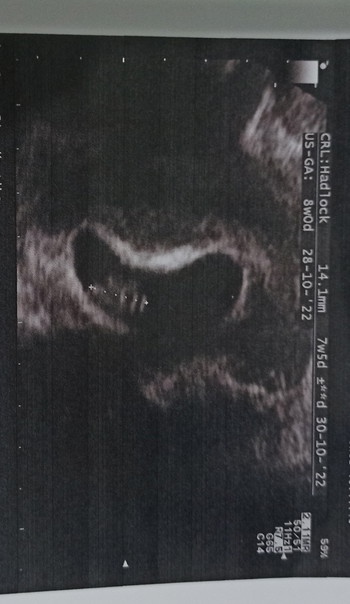

Ini adalah kehamilan kedua, saat ini saya memiliki anak pertama usia 3 tahun. Menurutku ini waktu yang sesuai untuk memiliki anak kedua, tidak terlalu jauh atau terlalu dekat.

Tiba saatnya saya merasa tidak nafsu makan, badan menjadi lemas, mual. Suami pikir ini efek dari covid, tapi perasaan berkata lain. Akhirnya saya coba untuk beli testpack, dan esok harinya coba tes di pagi hari. Alhamdulillah, hasilnya positif.

Kehamilan kedua saya ini berbeda sekali dengan yang pertama. Dulu saya tidak kenal lelah, makan apa saja enak, tidak mual, seperti wanita tidak hamil semua terasa biasa saja. Tapi hamil kedua ini, dari awal trimester 1 saya selalu merasa mual, badan cepat lelah, moody, tidak nafsu makan, dll.